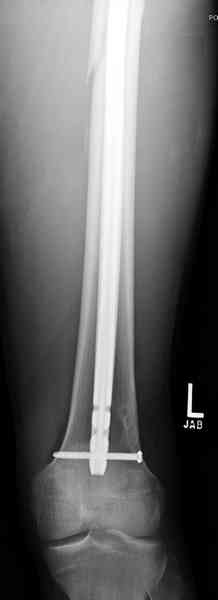

В приложении пример огнестрельного ранения бедра, оперированного на 2 сутки после ранения.

Штифтование было выполнено только на вторые сутки по причине задержки перевода из другого госпиталя, АБ профилактика была начата в другом учреждении, с момента госпитализации пациента к ним. Входное пулевое отверстие и зона введения штифта зажили первичным натяжением.

В конце 90-ых попалось несколько статей по nail exchange procedures in treatment of posttraumatic osteitis и решился попробовать на огнестрельных переломах, которые до этого лечил по полной схеме:расширенный дебрайдмент+ внешняя фиксации+промывные системы с антибиотиками и без антибиотиков в промывной среде. Всё заканчивалось длительной госпитализацией, плохими функциональными результатами( страдала функция колена), необходимостью повторной хирургией - отсроченная внутренняя фиксация переломов, длительной реабилитацией. На гвоздях процесс пошел лучше: остеомиэлитов не было и больные мобилизовывались быстрее.

Единственно что наблюдал - замедленная консолидация, судя по серийным Рг граммам. В приведенном случае прии вялом мозолееобразовании сделал ошибку, решившись динамизировать гвоздь - перелом сросся со значительным укорочением бедра - повторная хирургия по удлинению бедра и проксимальным запиранием, больной мобилизован и вполне доволен(кстати заметить больной с ВИЧ инфекцией - изначально скомпрометированный иммунитет и несмотря на это, всё прошло без костной и мягкотканной инфекции.